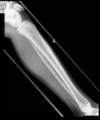

Osteoma Osteóide - A TC mostra o nidus radioluscente, cercado por reação esclerótica e , as vezes, pode mostrar um ponto esclerótico dentro do nidus.

Predomina 10 - 30 anos.

Nicho radiotransparente < 1cm circundado por reação esclerótica. Localização cortical / justacortical em ossos longos: femur proximal e tibia.

Clinica tipica: dor mais intensa a noite aliviada por AAS.

Quando nidus > 2cm = osteoblastoma. TC é a modalidade de escolha (RM pode não ver o nidus).